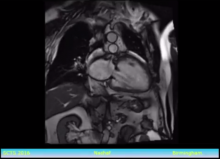

Samer Nashef of Papworth Hospital, Cambridge, UK, discusses the indications for surgical treatment of atrial fibrillation and explores the reasons for a wide variation in practice. He gives preliminary findings from a UK trial.